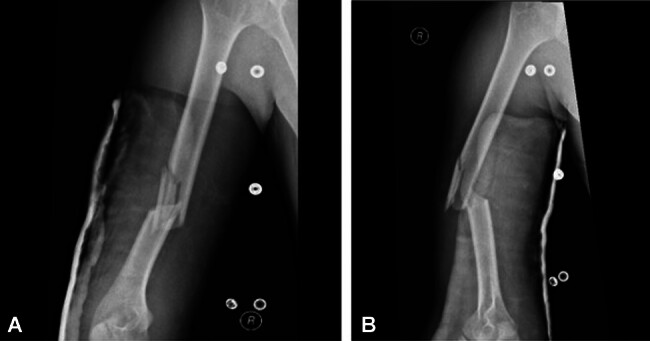

Abstract Image